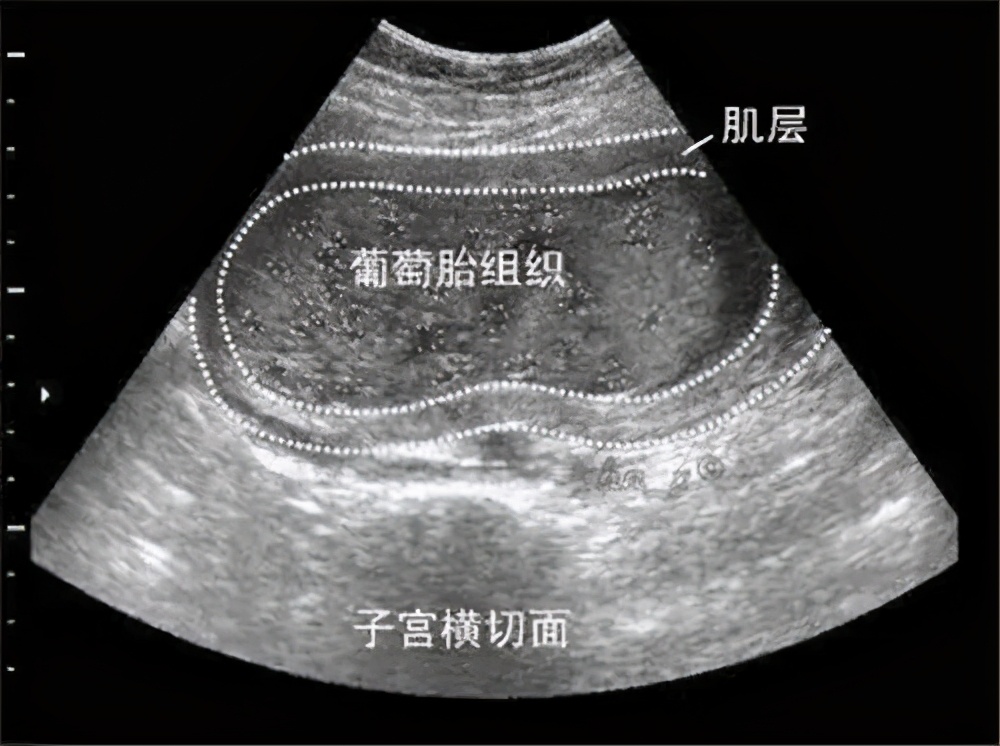

葡萄胎因妊娠后胎盘绒毛滋养细胞增生、间质水肿,而形成大小不一的水泡,水泡间借蒂相连成串,形如葡萄而得名,又称水泡状胎块。

葡萄胎一般在怀孕40~50天左右到医院做B超就可以发现, 停经后阴道流血是葡萄胎最早和最常见的症状,发生率一般在98%以上。